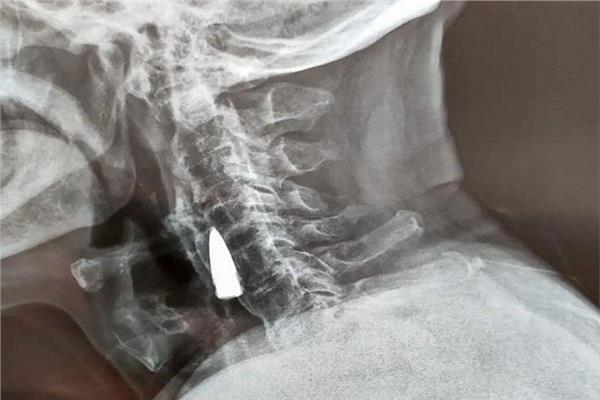

وبعد سماع الأطباء خبر سقوطه، أوصى الأطباء بإجراء أشعة سينية للتأكد من عدم تعرضه لأضرار جسيمة في رقبته لكن الأشعة السينية كشفت عن جسم غريب في رقبة الرجل، والذي تم تشخيصه لاحقًا على أنه رصاصة قديمة.

وبعد فحص الأشعة السينية ، أخبر الأطباء "زاهو هي" وعائلته أن الرصاصة كانت قريبة من بعض الأوعية الدموية الرئيسية وأنه نظرًا لأنها لم تسبب له أي مشاكل ، فمن الأفضل تركها وافق المحارب القديم.